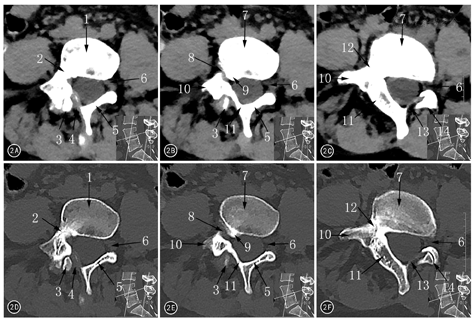

患者女,36岁,因"间断性右侧腰腿痛8年余,再次发作3个月",于2016年8月1日来海军总医院骨科就诊。曾在外院行腰椎平片及CT检查示腰骶椎隐裂(原始影像资料丢失),难以找到病痛的原因。查体:约平L4~5棘突间隙右侧压叩痛,向右下肢放射,右股神经牵拉试验阳性,右小腿内侧感觉减退,呈L4神经根受损体征。患者在我院行腰椎X线摄片检查报告示:L4~5椎间隙变窄,L5及S1隐裂。笔者阅读我院X线片,发现腰椎区域实际有以下多处形态及结构异常:正位片(图1A)示腰椎呈S形弯曲;L1~3以L2为顶椎右侧凸,似姿势性侧凸,但L3右椎板及下关节突发育肥大;右L3~4椎板间隙降至右L4椎弓根上界高度;以L4~5椎间隙为顶椎左侧凸,有多处解剖畸形。解剖畸形包括:(1)椎弓根,L4右侧椎弓根低于左侧;L4~5右侧椎间孔高度明显小于左侧。(2)横突,右侧L4横突发育小且低于左侧。(3)椎板,右侧L4及L5椎弓根向内共同发出一椎板结构,即L4~5椎板融合体,无右L4~5椎板间隙;右L4~5椎板融合体向中线上方移行,在棘突中线同左侧L4椎板融合,而左侧L5椎板游离,在中线略偏右同L4~5椎板融合体隔一左上斜向右下的裂隙,易误判为L5隐裂;右侧L4~5关节突关节辨不清。侧位片(图1B)示L4~5椎间隙变窄,L4~5椎间孔下方似有骨样突起。左斜位片(图1C)能辨出L4~5关节突关节;右斜位(图1D)示L4~5关节突关节结构消失。过伸过屈位片(图1E、图1F)示L4~5节段无活动度。腰椎CT检查及重建影像报告仅提及腰骶椎隐裂。笔者阅读CT横断面图像,未见到L3~S1节段有椎间盘突出;但对L4~5椎间隙节段的横断面连续CT图像观察发现L4~5右侧椎间孔前后径变小,自L5椎体右后缘有骨性隆起使椎间孔呈迂曲状,右侧L4~5椎板融合体宽度明显为厚(图2)。矢状位CT重建见右侧L4~5椎间孔周径明显变小,L4~5关节突关节融合(图3)。冠状位CT重建图像证实右L4~5关节突关节融合,右侧L4椎弓根平面下降,右侧L4横突发育不良,右侧L4~5椎板融合(图4)。患者经卧床休息、脱水及激素冲击治疗,右侧下肢放射痛减轻。建议行腰椎MR或腰椎管造影了解神经根走行有无异常,患者因症状缓解拒绝再行进一步检查。随访3个月,期间右侧下肢放射痛复发1次,但未达到3个月前强度,口服镇痛消肿药物及卧床休息后,症状再次好转。患者暂未手术,继续随访观察中。